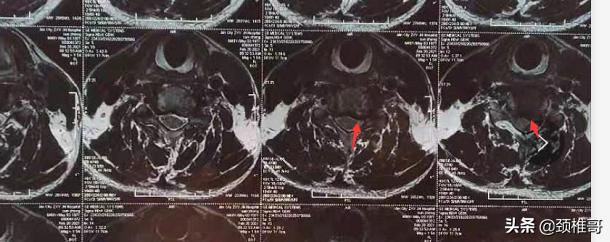

1 脊髓受压程度(在你看过的影像算严重的么?),C56位置椎管还有空间了吗?

1 如果仅仅是从影像学来看 是算有点严重的, c56 椎管没有空间了 如箭头所示